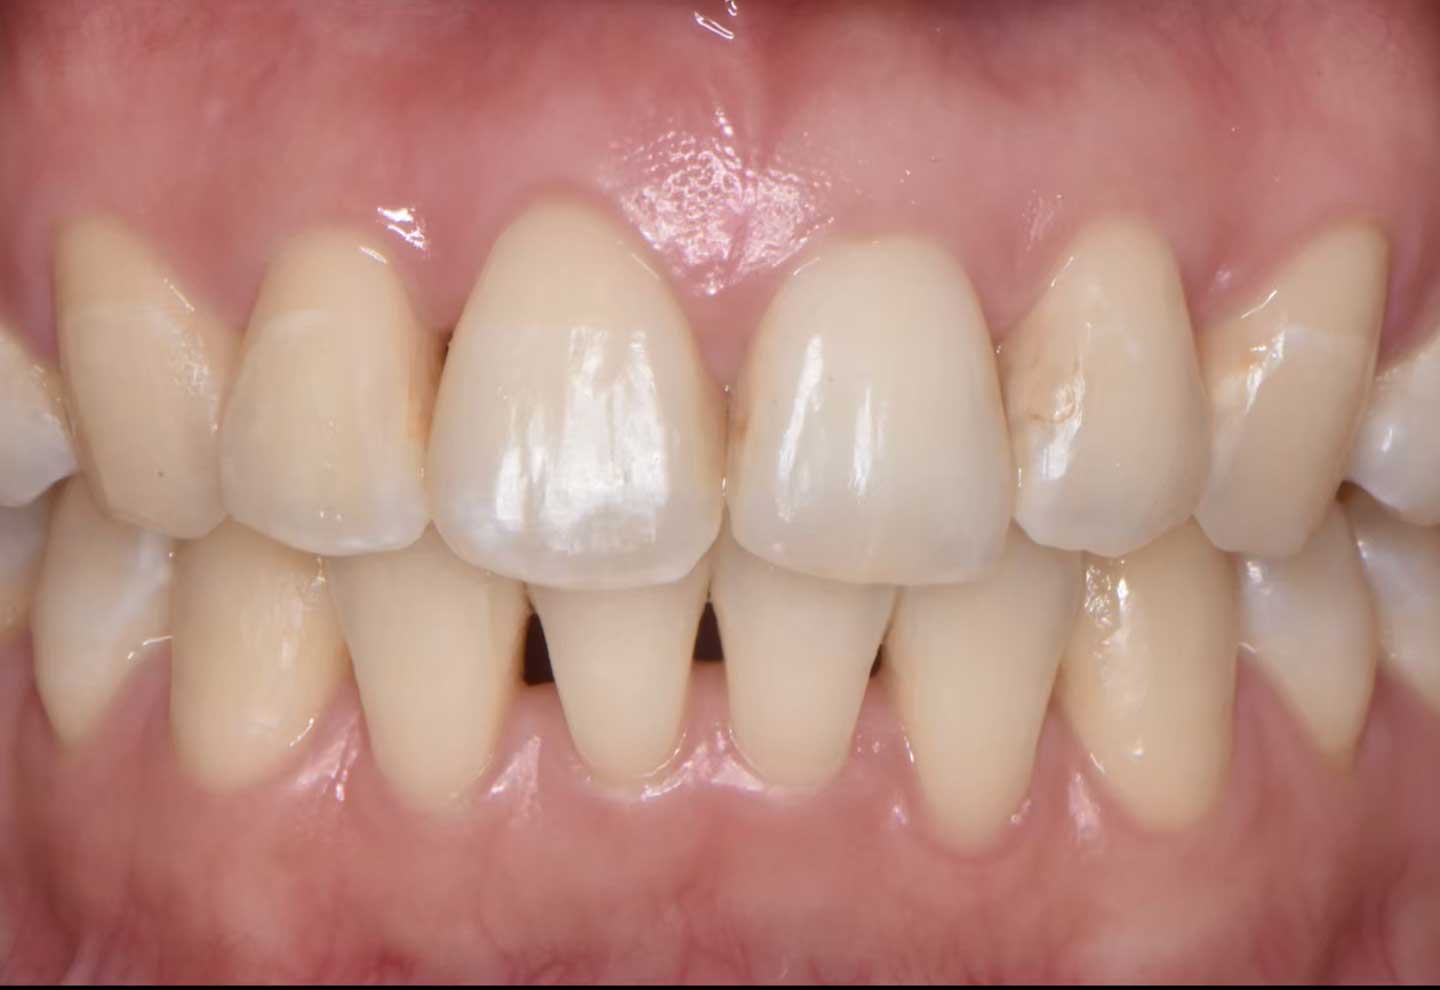

e-max(改良型オールセラミック)症例

| 治療内容 |

e-max治療 |

| 治療期間 |

型取りから約3週間 / 型取りとセットで2回 |

| 費用 |

82,500~165,000円(1歯)※自由診療 |

| リスク・副作用 |

・自由診療になります。

・歯を削る必要があります。

・強い咬合力や歯ぎしりにより欠けたり割れる可能性があります。 |